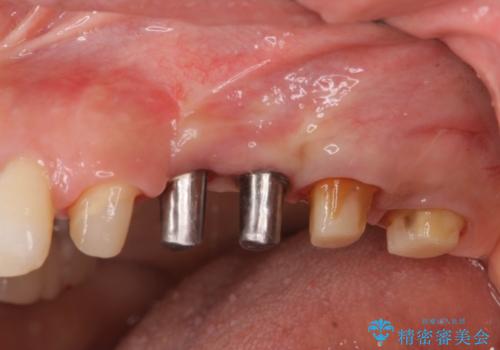

銀歯を外してのインプラント・セラミック治療

- 長年気になっている銀歯を外したい、と希望され来院されました。

銀歯を除去したところ大臼歯は十分な歯質が残っていたため残すことができましたが、小臼歯の2本は虫歯の再発により残っている歯質が非常に少なく破折リスクが非常に高いと判断しました。

長期的な予後を見込むことが難しいため、相談の上抜去を行いインプラント治療を進めていくこととなりました。